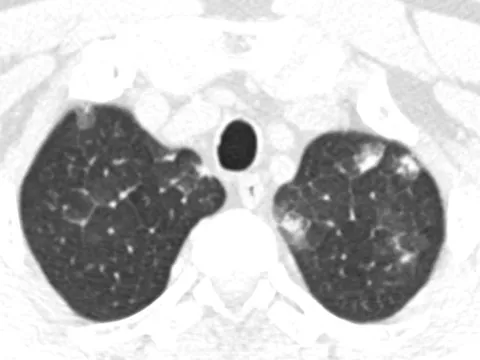

Nữ giáo viên sốc khi phát hiện mắc ung thư phổi, chia sẻ 3 dấu hiệu đã trải qua

Nữ giáo viên không hút thuốc và có lối sống lành mạnh nên đã rất bất ngờ khi được chẩn đoán ung thư phổi.